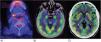

Observación clínicaCaso 1: paciente mujer de 68 años de edad, que comenzó con pérdida del estado de alerta, desorientación, ideas delirantes, alucinaciones visuales y crisis tónico-clónica. En la RM de encéfalo se identificaron lesiones en los lóbulos frontales de características puntiformes e hiperintensas en secuencias T2 y flair, así como disminución del volumen cerebral cortical de tipo frontal. Durante su estancia hospitalaria presentó crisis gelásticas, por lo que se le realizó un electroencefalograma en el que se reportó: trazo anormal con disfunción difusa, de características ictales, de inicio eléctrico, de ritmo reclutante en rango delta seguido por actividad de puntas en regiones posteriores bilaterales, con predominio derecho, por lo que se inició tratamiento con levetiracetam y se determinaron anticuerpos anti-Smith, anti-SS-A y anti-SS-B negativos, ANA totales positivos 1:640 con patrón moteado fino denso. Se realizó PET-TC como complemento del abordaje, en el que se reportó hipometabolismo cerebral generalizado, así como incremento en la captación de ganglios basales (fig. 1A). Se realizó biopsia glandular salival con reporte de atrofia de acinos mucinosos con foco de infiltrado linfoide moderado de más de 50 linfocitos, así como datos de fibrosis, ectasia ductal y abundantes cuerpos apoptóticos (fig. 2). Se inició manejo con bolos de metilprednisolona y posteriormente rituximab, presentando mejoría clínica.

A) Tomografía por emisión de positrones (PET-TC) del caso 1. Se observa alteración en la densidad de las glándulas salivales que se correlaciona con enfermedad de Sjögren, con un foco de metabolismo incrementado en la glándula submandibular derecha de 10mm con SUVmáx de 5,8. B y C) PET-TC del caso 2. Se observan, con aumento del metabolismo en ambos hipocampos, la corteza temporal derecha y ambos putámenes. El resto de la corteza se observa con hipometabolismo generalizado.

Caso 2: paciente mujer de 20 años de edad sin comorbilidades previas, quien presentó de manera súbita pensamiento desorganizado, contenido pobre del discurso, delirio de persecución, alucinaciones auditivas, desorientación, así como síndrome catatónico, caracterizado por hipomimia, mutismo, anergia y apatía. Presentó un intento suicida de alta letalidad, con posterior manejo farmacológico por parte de psiquiatría. Se le realizó PET-TC en la que se documentó corteza occipital lateral con disminución en el metabolismo, núcleos caudado y putámenes con incremento metabólico, así como cerebelo con hipometabolismo generalizado (figs. 1B y C). Anticuerpos de encefalitis autoinmune negativos. ANA totales con titulación 1:320 con patrón moteado fino denso, anti-DNA DS 34,5UI/ml, anti-SS-A 153,6UI/ml y anti-SS-B negativos. Se inició tratamiento con bolos de metilprednisolona. Cuatro meses después de su egreso presentó mutismo acinético, incapacidad para la realización de las actividades diarias e incoordinación, por lo que se le realizó plasmaféresis, con mejoría del cuadro.